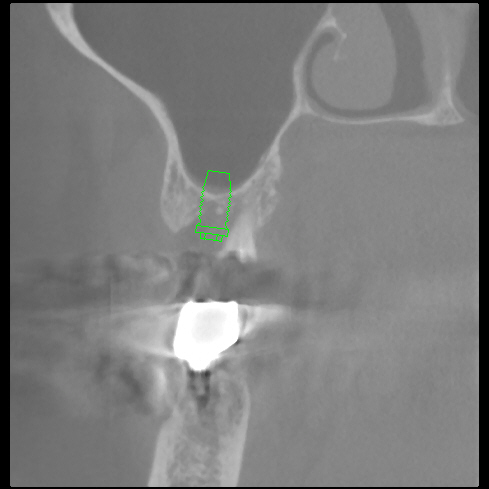

患者様の状態・ご希望 「右上の奥歯が取れちゃった」「ほとんど根っこが残っていないみたいなの。」 20年以上メンテナンスにかよってくださっている患者様です。 「私の上あごって上顎洞があって骨が薄いんでしょ」 「左上の奥歯の時はお世話になりました、苦労してオペしていただきまし…